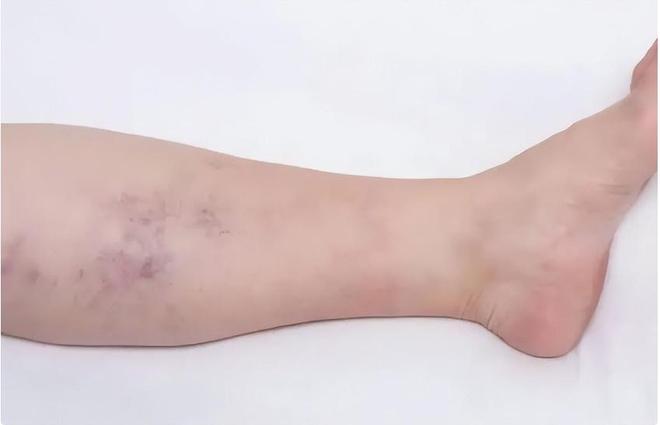

起初,她以为是前几天运动时不小心扭伤的缘故,并没有过多在意,强忍着疼痛继续完成了当天的课程。

医生经过一番详细检查后,告诉李明馨和她的母亲:“你女儿的腿里发现了肿瘤,而且已经是恶性。”